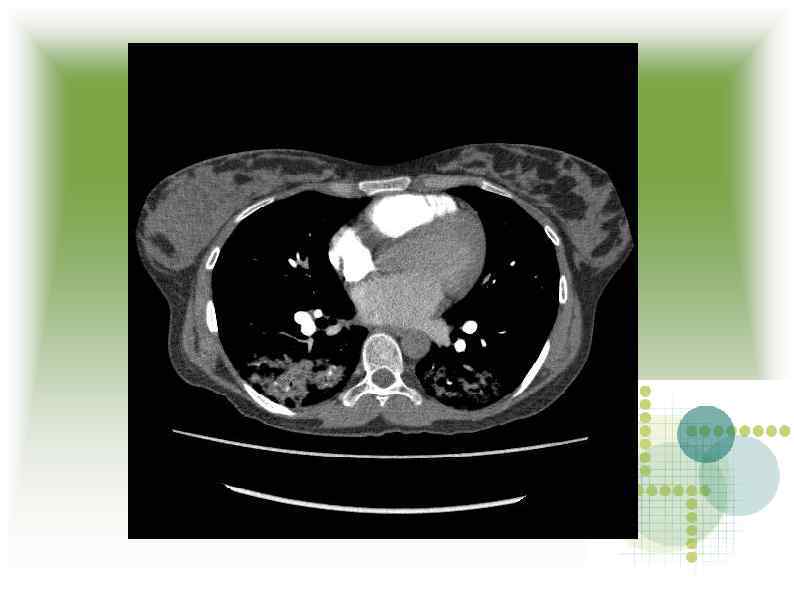

МСКТ МСКТ

Заключение МСКТ Признаки геморрагической пневмонии? Заключение МСКТ Признаки геморрагической пневмонии?